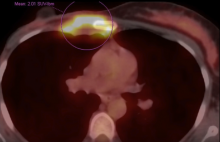

This video demonstrates a sternal resection, followed by reconstruction with a titanium mesh, for a local recurrence of breast cancer. Anterior chest wall involvement after mastectomy in patients with breast cancer is an uncommon situation. Surgical excision is an important part of the multimodality treatment of the local recurrence of breast cancer. Yet, the large defect after resection of the sternum and the ribs constitutes a major challenge. Among the options in covering the anterior chest wall after sternal resection, titanium mesh may be preferred with its "easy to implant" feature. In this short video, the authors present a sternal resection and reconstruction with titanium mesh in a 41-year-old female patient, who had a local recurrence of the tumor three years after surgery and chemotherapy for breast cancer.